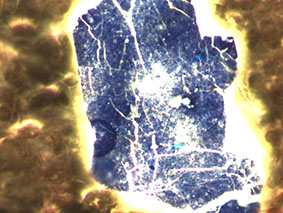

Aspergillus mit Schwermetall-Belastung